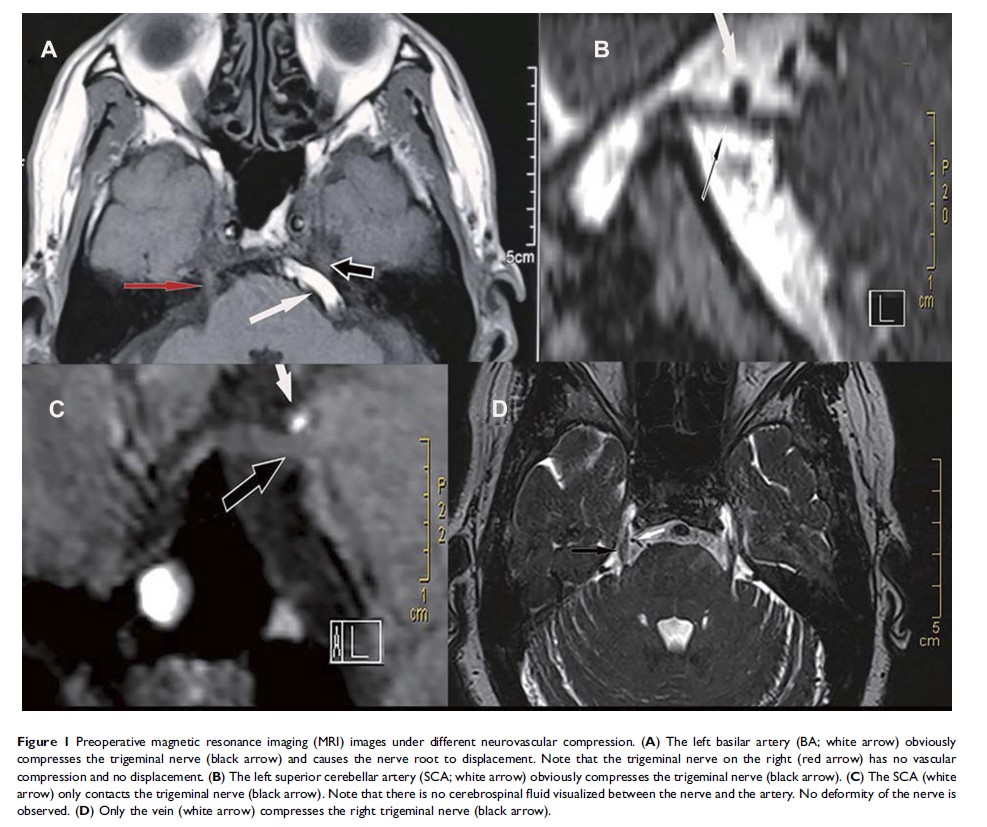

微血管减压术结合感觉根部分切断术与否对三叉神经痛治疗长期疗效和预测因素的比较